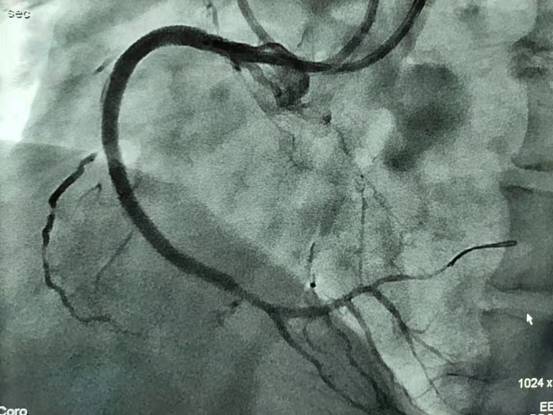

冠状动脉慢性完全闭塞病变(CTO)是介入心脏病学最具挑战的领域,近年来我院多次与日本、上海、杭州等多地的专家交流学习,CTO病变的手术成功率稳步提升。2021年8月3日及2021年8月31日,在匡永东主任医师的指导下,由陈世志主治医师、姜进克副主任医师共同完成了2例CTO逆向冠脉介入治疗,为我院首次自主开展的逆向CTO介入治疗,其中一例还是难度及风险均极大的经心外膜侧枝逆向CTO介入。

术前

术后

以前只能在手术转播中或外请专家时才能看见的技术被我们较熟练的运用,并取得的很好的效果,说明我院的冠脉介入水平能紧紧跟住省级医院的水平。